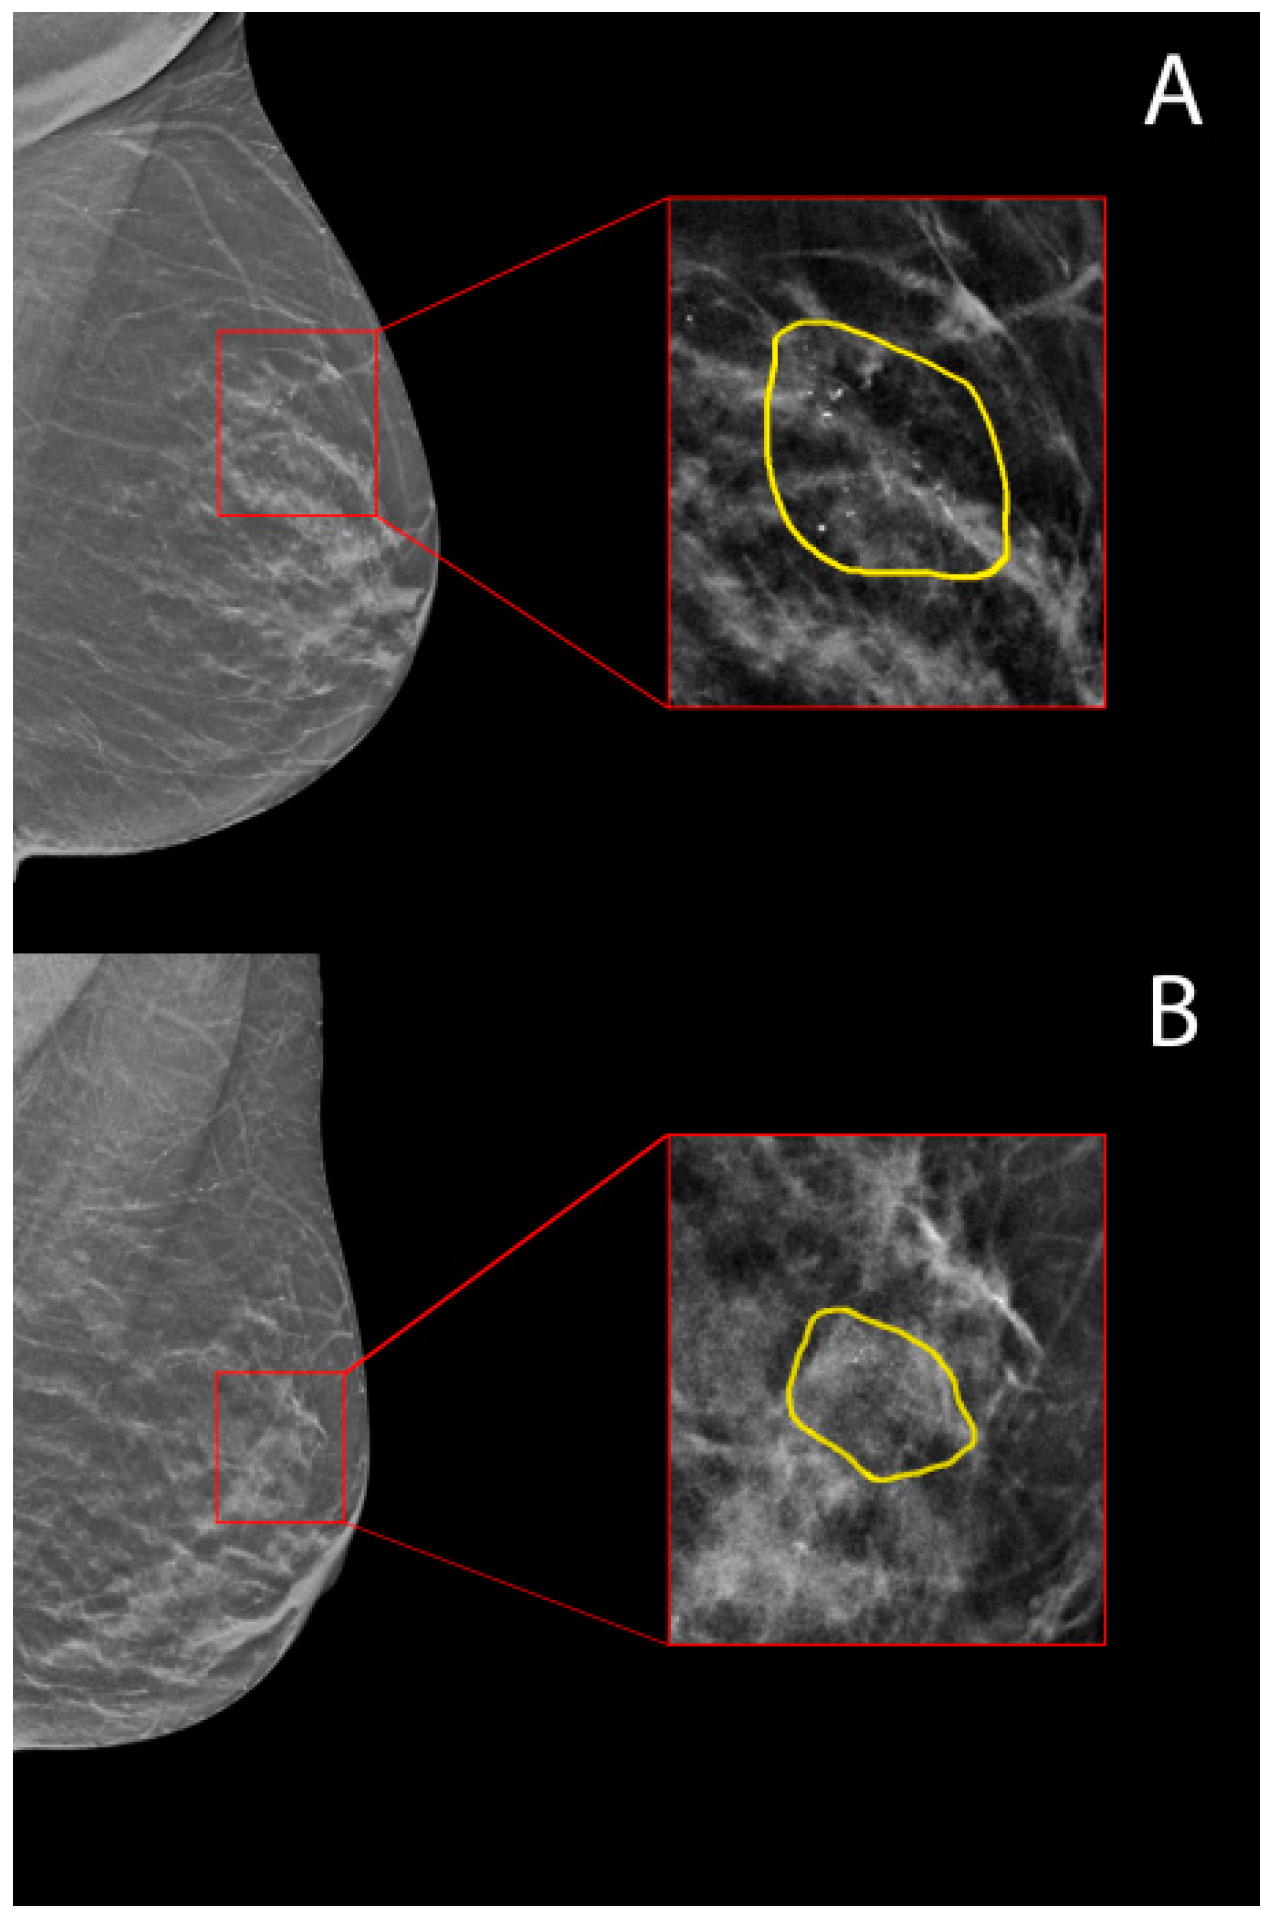

Figure 1A,B shows, as representative examples, two ROIs manually segmented by the expert radiologist on two different DBT images for two calcifications then diagnosed as a malignant lesion and benign cancer lesion, respectively, at their histopathological reports (DBT-guided VAB).

Figure 1. Manual segmentation of the Region Of Interest (ROI) on digital breast tomosynthesis (DBT) images for: (A) a malignant calcification, and (B) a benign calcification, according to their histopathological reports (DBT-guided vacuum-assisted biopsy (VAB)) and follow-up.